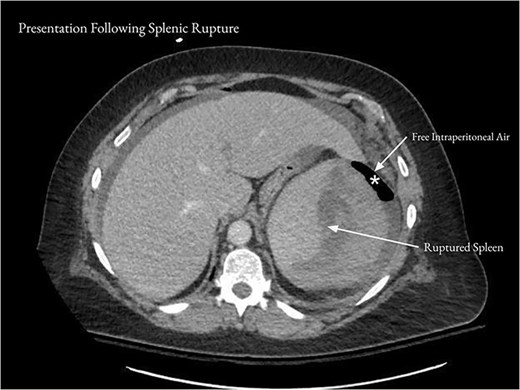

On examination, the patient appeared mildly ill and uncomfortable. Blood pressure was 132/81, heart rate was 107, and temperature was 37.8°C. The abdomen was soft, with moderate left upper quadrant and left flank tenderness, mild distention, and no guarding. Laboratory workup revealed a white blood cell (WBC) count of 13.2 × 103/μl, a hemoglobin of 13.5 g/dl, and a hematocrit 36.0%. Computed tomography (CT) of the abdomen and pelvis with contrast showed acute diverticulitis of the splenic flexure with moderate wall thickening. There was adjacent extraluminal gas consistent with localized perforation (Fig. 1).

Computed tomography of the abdomen and pelvis on presentation showed acute diverticulitis of the splenic flexure with moderate wall thickening and adjacent extraluminal gas consistent with localized perforation.